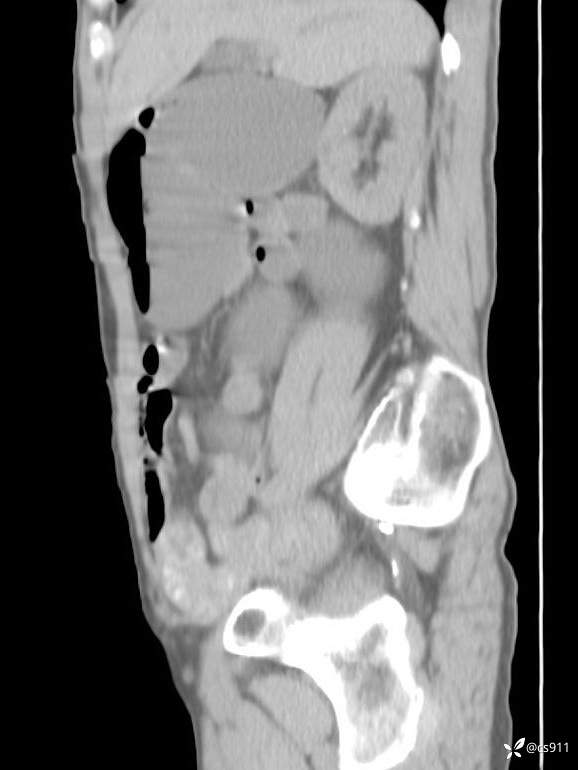

急腹症之急诊CT,原因?答案公布

男,77岁,腹痛、腹胀伴恶心呕吐1天。呕吐胃内容物,非喷射性呕吐,有咖啡色样胃内容物,诉有胃穿孔病史。查体:全腹平,下腹部压痛,全腹无反跳痛,叩诊呈浊音,移动性浊音阴性,肠鸣音减弱,1-2次/分。肛检:直肠未扪及明显肿物,可触及大量粪块。

T 36.6℃ P 80次/分 R 26次/分 BP 100/60mmHg

白细胞(WBC) H 14.55 10e9/L 4-10

红细胞(RBC) 4.58 10e12/L 4.3-5.8

中性粒细胞百分率(NEUT%) H 85.7 % 40-75

血淀粉酶(AMY) HH 1859 U/L 35-135

癌胚抗原(CEA) H 27.44 ng/ml 0-5

呕吐物 潜血试验 * 阳性 阴性

患者轮椅入室检查神志清楚, 能配合摆位和呼吸